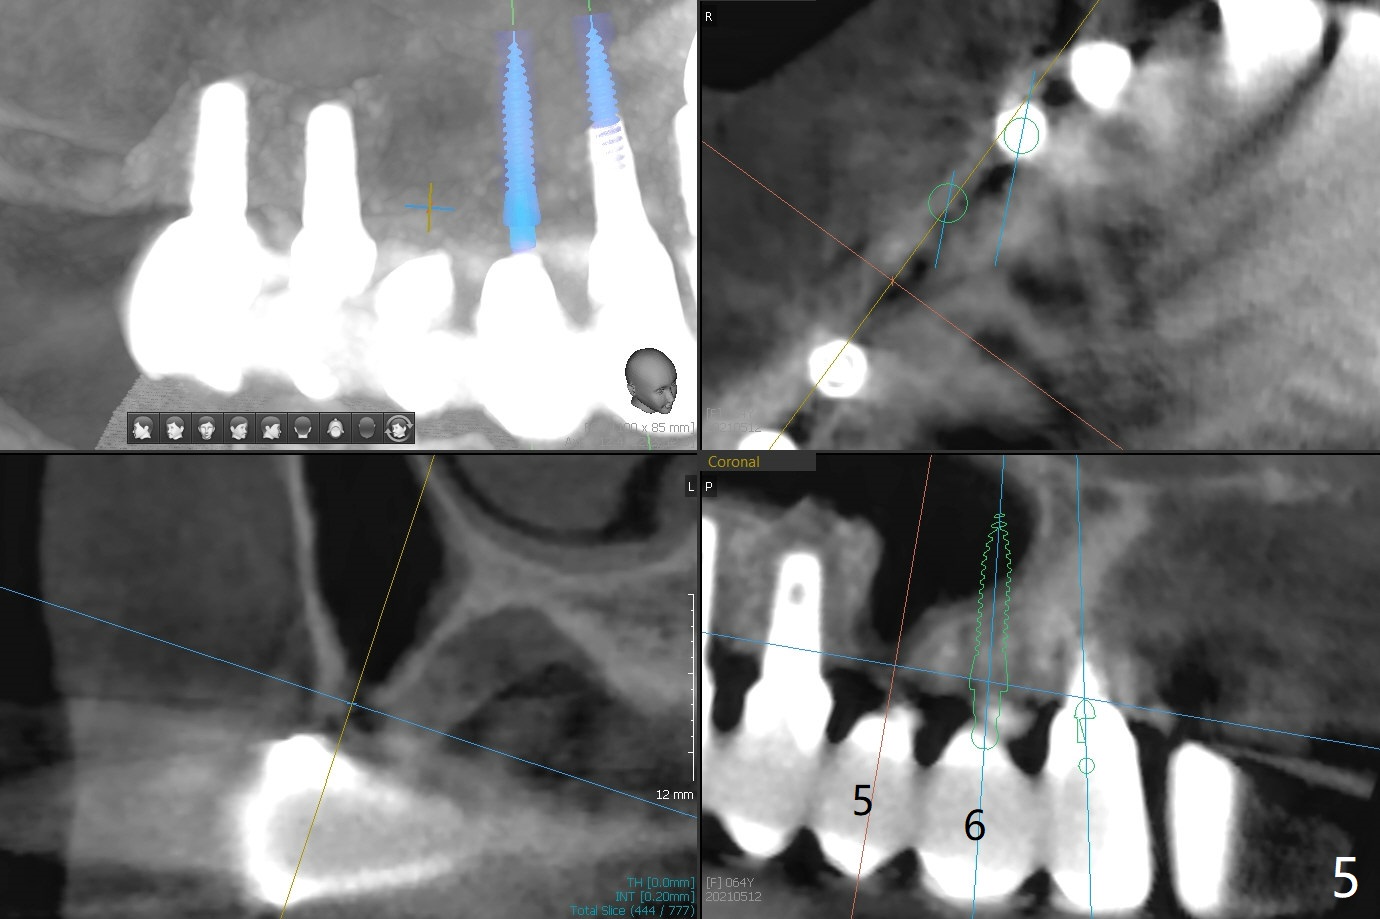

64岁女#3-7,8-13植牙桥多年,7-8之间出现间隙(图一),最近7颊侧牙龈出血,CT显示7颊侧骨板缺失(图二,三)。可能植骨有困难,似乎2x12毫米植体是解决问题部分措施(图四),接着外提升,在5,6上颌窦植骨,如果顺利,同期在6种植,2x10毫米(图五),3-5暂时改为悬臂桥,如果5提升成功,再种植一个植体。但是病人要求植骨。Return to Protect Graft 101 Xin Wei, DDS, PhD, MS 1st edition 05/12/2021, last revision 06/15/2021